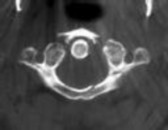

Figure 1 shows a CT from the cervical spine of an 85-year-old woman who fell from a standing height 1 week earlier. She is independent and ambulatory and resides in an assisted living facility. She reports persistent neck pain but denies arm pain or weakness. She is neurologically intact.

Fractures in this region of C2 have a high risk of

Discussion: C

Increased displacement and angulation of odontoid fractures have an increased risk of nonunion. Surgical stabilization has reduced the risks of mortality without increasing the risk of complications compared with nonsurgical treatment options. When treating odontoid fractures, halo vest

immobilization has been shown to increase the risk of dysphagia in the elderly.

The preferred mode of treatment for this patient’s fracture is

1. a halo vest.

4. posterior C1-2 arthrodesis. Discussion: D

Increased displacement and angulation of odontoid fractures have an increased risk of nonunion. Surgical stabilization has reduced the risks of mortality without increasing the risk of complications compared with nonsurgical treatment options. When treating odontoid fractures, halo vest immobilization has been shown to increase the risk of dysphagia in the elderly.

What are the risks associated with halo vest treatment, compared with hard-collar treatment?

4. Dysphonia Discussion: B

Increased displacement and angulation of odontoid fractures have an increased risk of nonunion. Surgical stabilization has reduced the risks of mortality without increasing the risk of complications compared with nonsurgical treatment